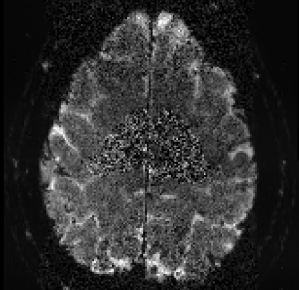

Screenshot 2018-01-08 15.38.38 renzohuber January 8, 2018January 8, 2018 Published by renzohuber View all posts by renzohuber Published January 8, 2018January 8, 2018